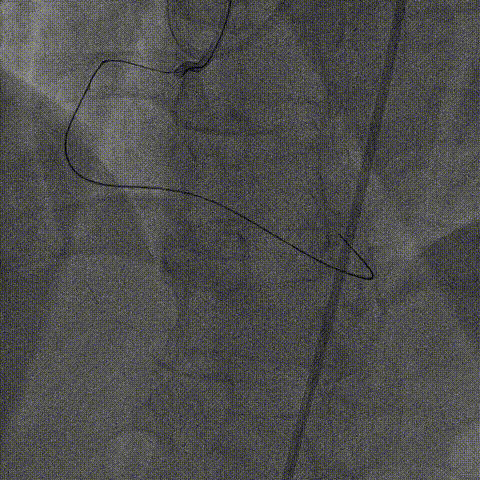

器械通过困难:

1、正向导丝通过后,微导管无法跟进,尝试1.25、1.5mm球囊均无法通过病变。

2、6F Telescope™导引延长导管支撑下1.25mm球囊通过病变预扩后换用2.0mm球囊完成预扩张。

右冠PCI

1、2.0mm球囊预扩张后球囊顺利进入Telescope™导引延长导管锚定导丝,送入Finecross微导管,后交换Pilot200导丝为Runthrough导丝。

2、6F Telescope™导引延长导管可兼容2号2.0mm预扩球囊及Finecross微导管同时进入,具有良好的内腔兼容性。

2.0mm球囊进入Telescope™锚定,通过无阻力

2.0mm球囊锚定导丝后微导管进入Telescope™内腔兼容性强